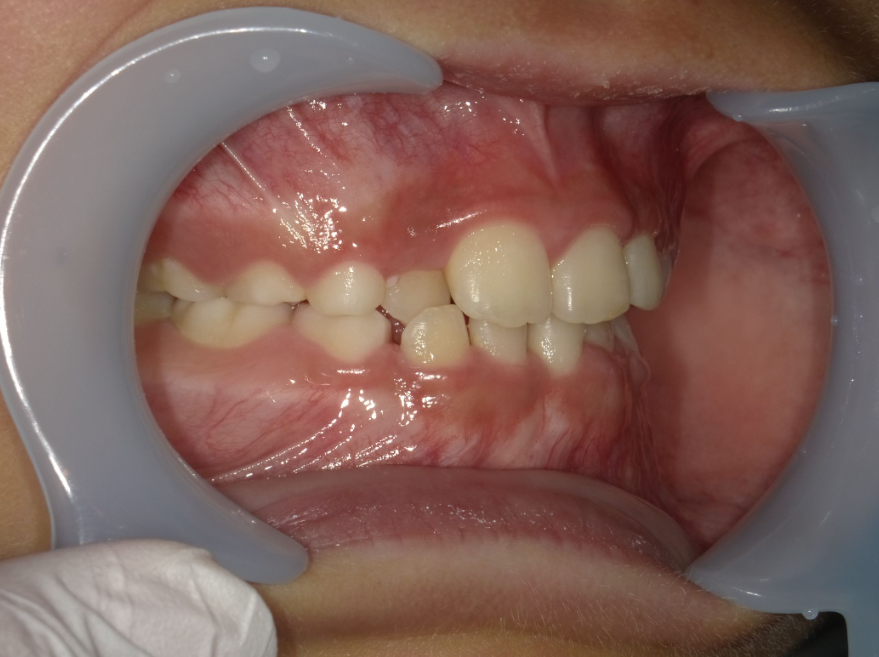

10代男性 叢生(歯のがたつき)・スペース不足・交叉咬合(一部分だけかみ合わせが反対)

治療内容:インビザライン・ファースト